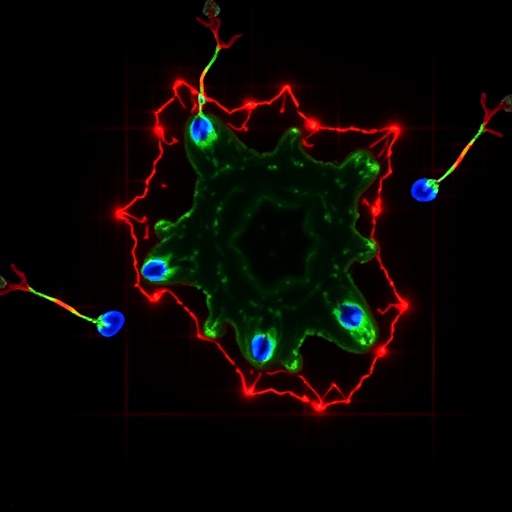

Self-Assembled Cardiac Organoids Model Heart Chambers

In a groundbreaking leap for cardiovascular research, scientists have engineered self-assembled chamber-like cardiac organoids that faithfully mimic the complex architecture...